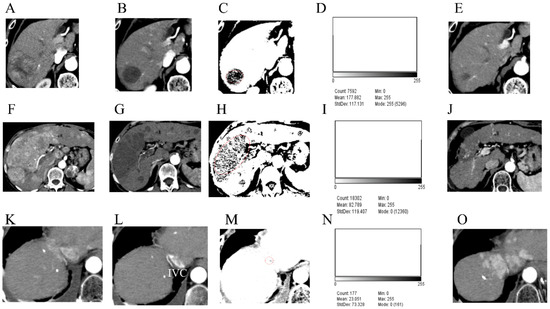

3.2. Preoperative Computed Tomography and Pathological Findings of the Resected Specimens

3.4. Case Presentations